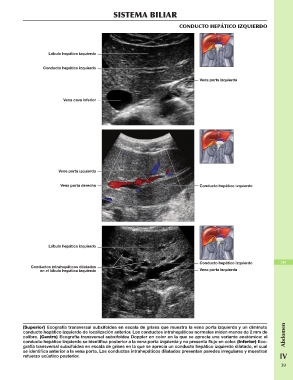

CONDUCTO HEPÁTICO IZQUIERDO

(Superior) Ecografía transversal subxifoidea en escala de grises que muestra la vena porta izquierda y un diminuto Abdomen

conducto hepático izquierdo de localización anterior. Los conductos intrahepáticos normales miden menos de 2 mm de

calibre. (Centro) Ecografía transversal subxifoidea Doppler en color en la que se aprecia una variante anatómica: el IV

conducto hepático izquierdo se identifica posterior a la vena porta izquierda y no presenta flujo en color. (Inferior) Eco

grafía transversal subxifoidea en escala de grises en la que se aprecia un conducto hepático izquierdo dilatado, el cual 39

se identifica anterior a la vena porta. Los conductos intrahepáticos dilatados presentan paredes irregulares y muestran

refuerzo acústico posterior.